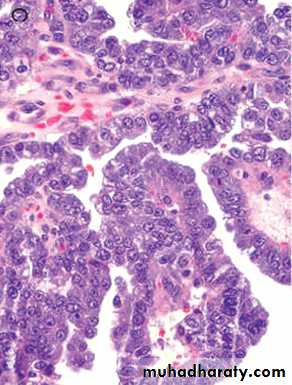

Serous carcinoma forms small tufts and papillary arrangements rather than the glands seen in endometrioid carcinoma, and has much greater cytologic atypia. They are particularly aggressive .

C, displaying formation of papillae and marked cytologic atypia. D, Immunohistochemical stain for p53 reveals accumulation of mutant p53 in serous carcinoma.

Serous carcinoma of the endometrium